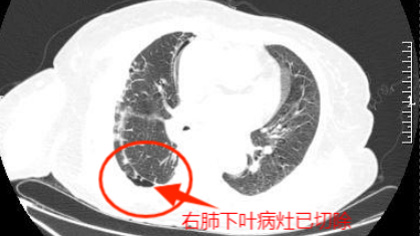

近年来,随着人们健康意识的提高和高分辨率CT的普及,肺结节的检出率呈明显上升的趋势,部分影像学提示高危结节的患者需要进一步活检明确性质,CT引导下经皮肺穿刺就是其中最常选择的检查方式。来凤县人民医院肿瘤科自开展该项业务以来,已为超过10名患者提供精确诊断,其中更有两例患者通过穿刺活检确诊为早期肺癌,已及时通过手术对原发肿瘤进行切除,目前恢复情况良好。〔全文〕